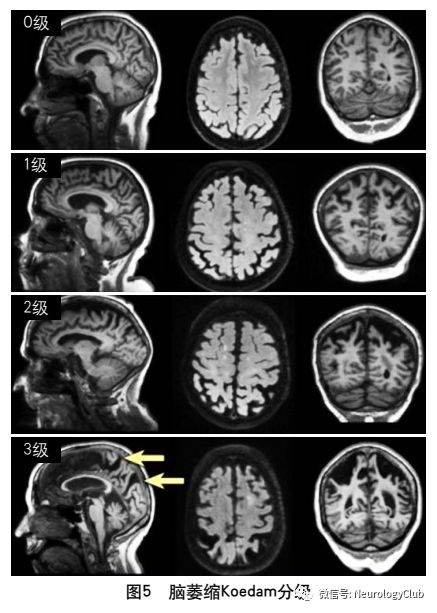

2013年的共识指南将脑萎缩定义为与特定的局灶性损伤,如脑外伤或脑梗死无关的脑容积减少脑萎缩可以是广泛的或局部的(如特定的脑叶或海马等特定区域),可以是对称或不对称的,亦可以是组织选择性的(如发生在白质等某一特定组织层)目前不同部位的脑萎缩有相应的诊断标准,全脑皮层萎缩分级用于评价全脑(图3);内侧颞叶萎缩分级主要评价颞叶内侧,重点是海马(图4);Koedam分级主要评价顶叶,尤其是扣带回和楔前叶(图5);Kipps/Davies分级主要评价额颞叶(图6)推测脑组织减少是由脑沟(周围)和脑室(中心)的脑脊液空间相对于颅内容积扩大所引起的